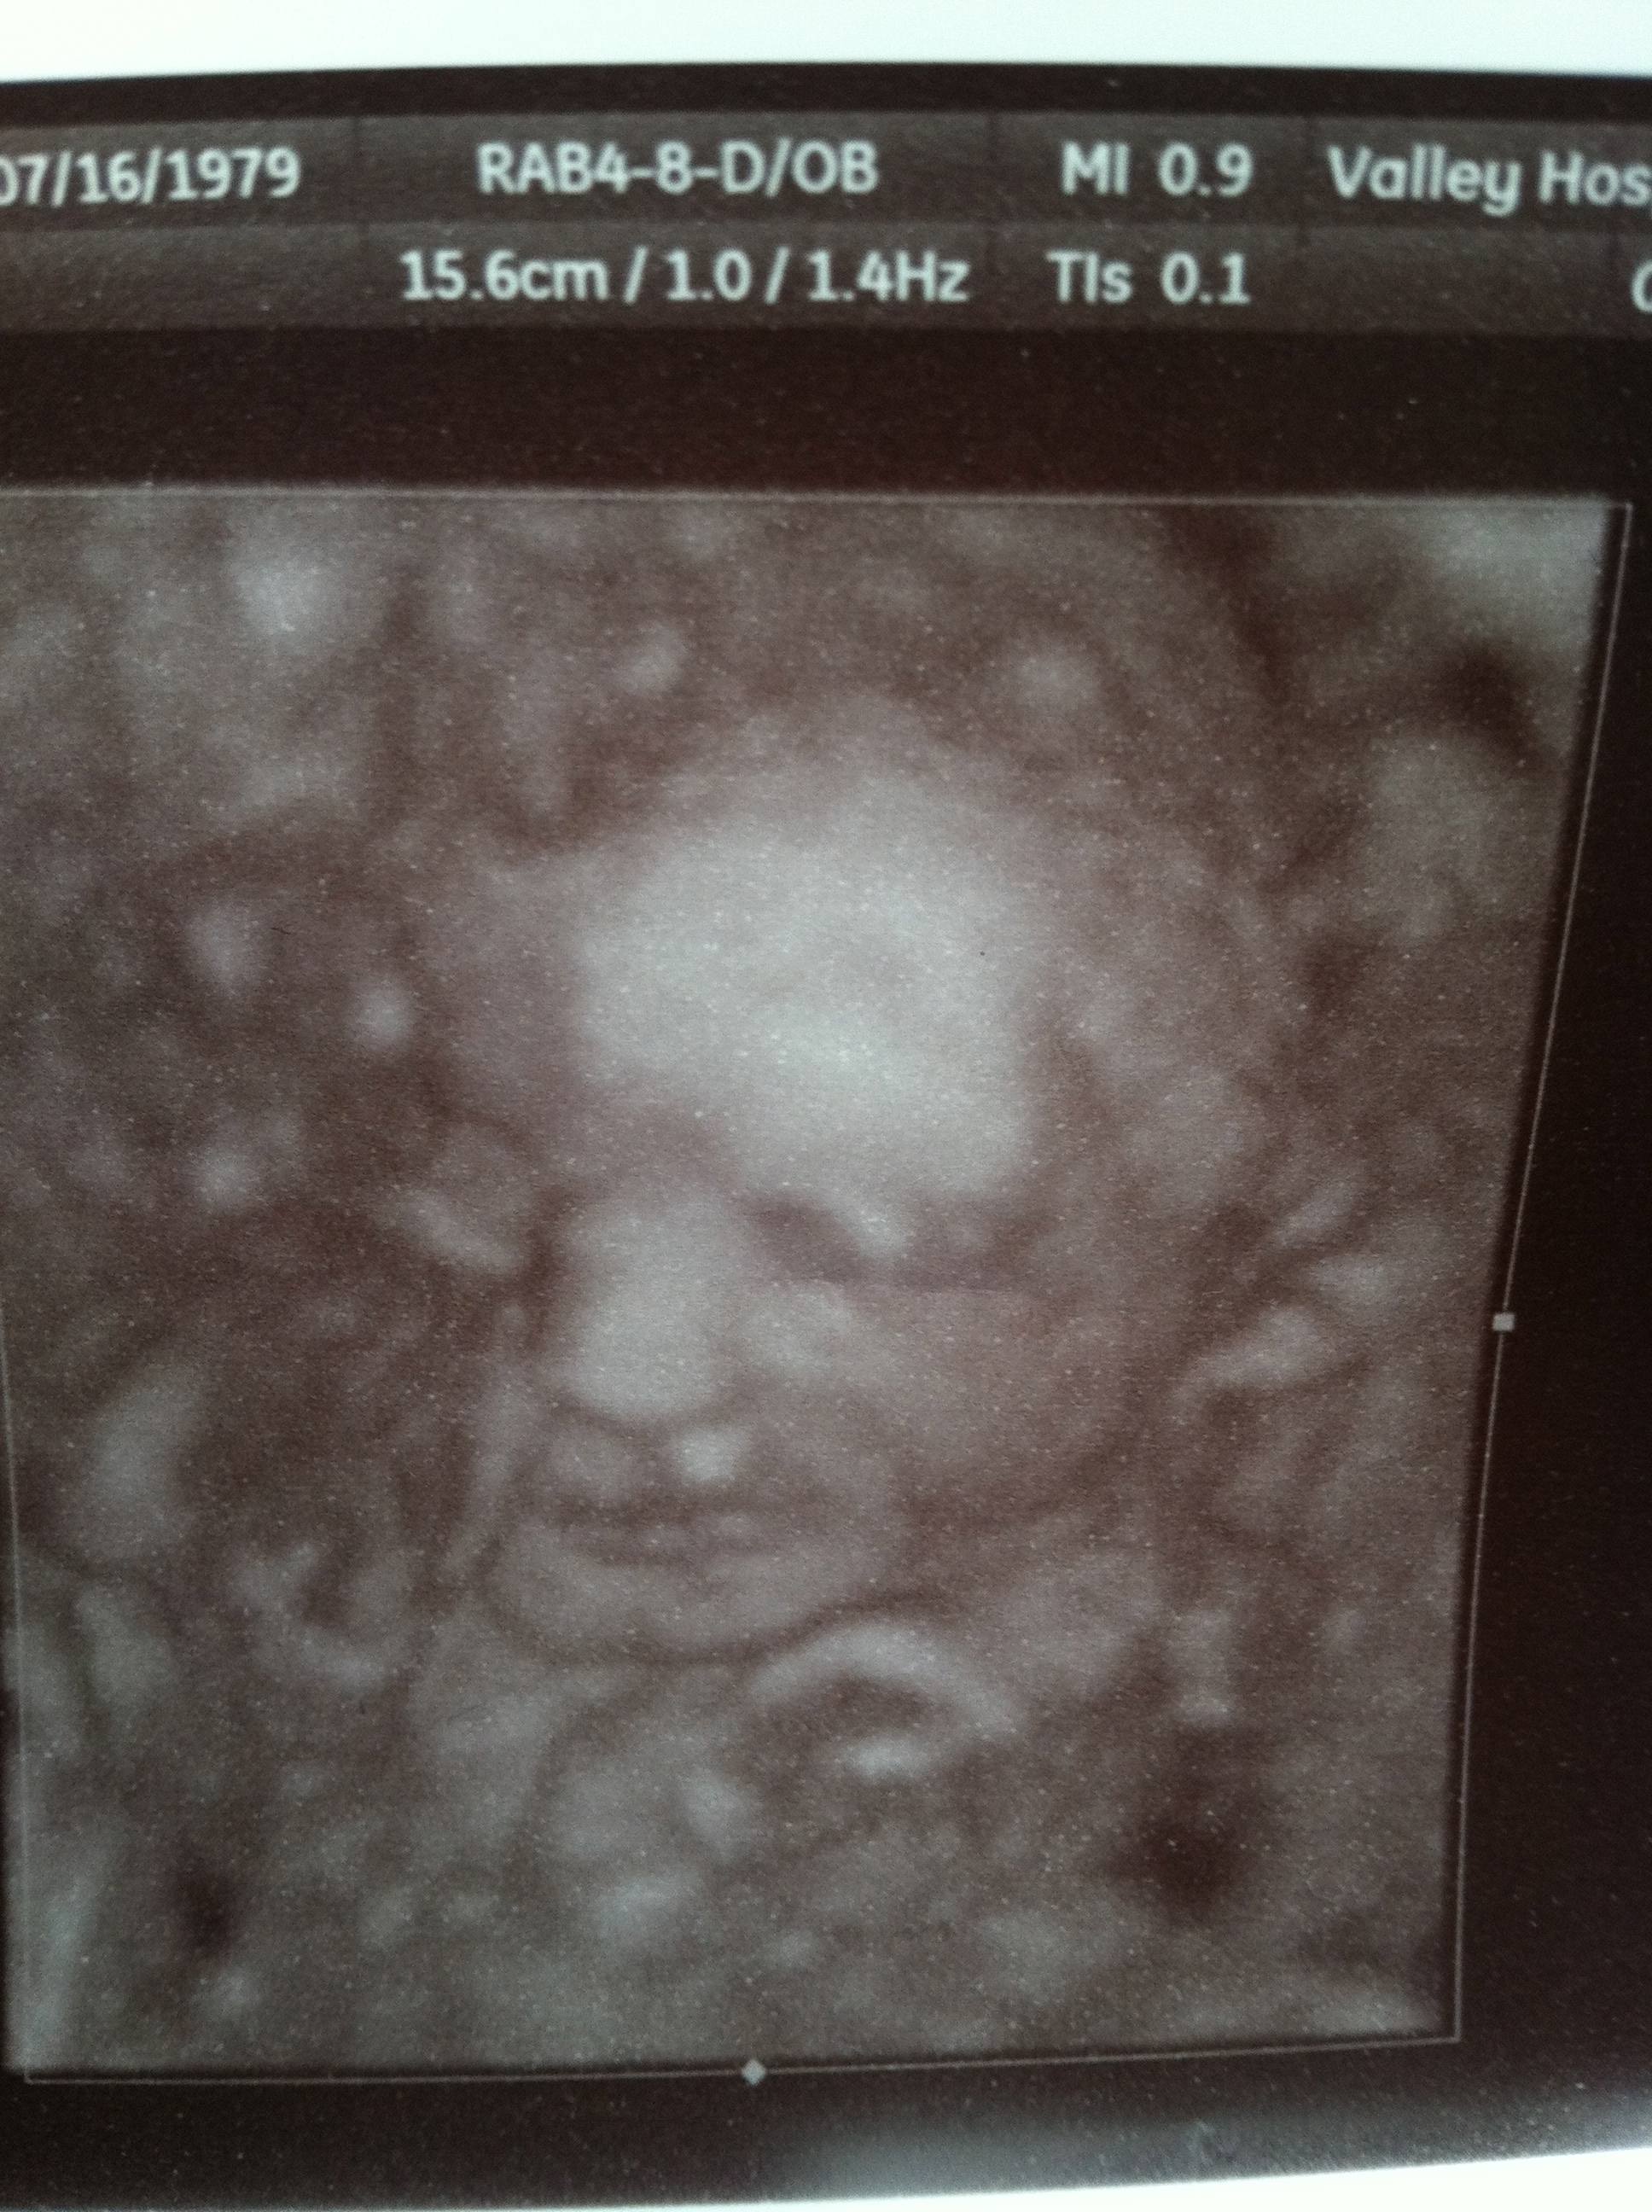

Any guesses? i know you cant tell much from face but who knows-maybe some of you have insight i dont! Hope everyone is feeling well and having blessed pregnancies.xAttachment 2515

Nothing that indicates gender but you have one gorgeous wee bubba in there!! So cute makes me very very clucky!!!!!!!!

No idea on gender, but what a SWEET little smile!